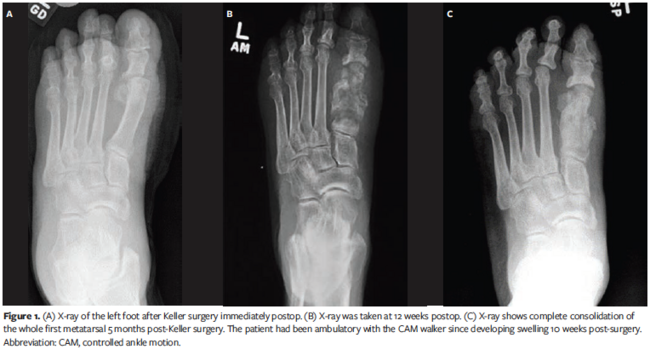

A 55-year-old male with a history of type 2 diabetes presented to the podiatry clinic with a foot ulcer lasting 3 months. Medical history included peripheral neuropathy, foot ulcers, hypertension, atrial fibrillation, and hyperlipidemia. He had palpable pedal pulses but lacked protective sensation. The DFU was located on the left plantar hallux interphalangeal joint, measuring 3 cm × 1 cm × 0.1 cm. It had mild edema and erythema but did not probe to the bone. The patient underwent weekly debridement, moist wound dressings, and offloading with felted foam in a postoperative shoe, but the DFU did not show improvement after 4 weeks. The patient underwent a left hallux Keller arthroplasty (Figure 1A). He was outfitted with a CAM boot and instructed to offload the left foot. The DFU healed in 2 weeks, but the patient developed dehiscence on the dorsal incision site. The wound was superficial and did not probe deep. The patient continued receiving wound care and offloading. The dehisced wound healed in 2 weeks. The patient returned to the clinic 2 months later, 10 weeks after the Keller procedure. The surgical site was closed but had mild swelling. Radiographs were not taken during this visit. The patient returned in 2 weeks, concerned that the left hallux had more swelling. He did not have an ulcer. The radiographic examination was read as having diffuse erosive and bony proliferative change concerning OM (Figure 1B). Still, the authors maintained that the clinical presentation was more consistent with a neuropathic fracture of CN. The patient was treated with strict offloading in a CAM boot, and the fragmented bone consolidated after 5 months (Figure 1C).